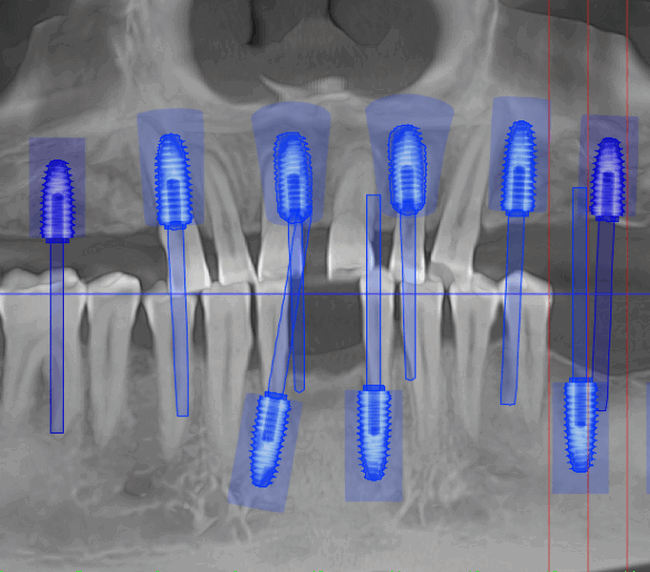

Tomografie (CBCT)

Caz 1